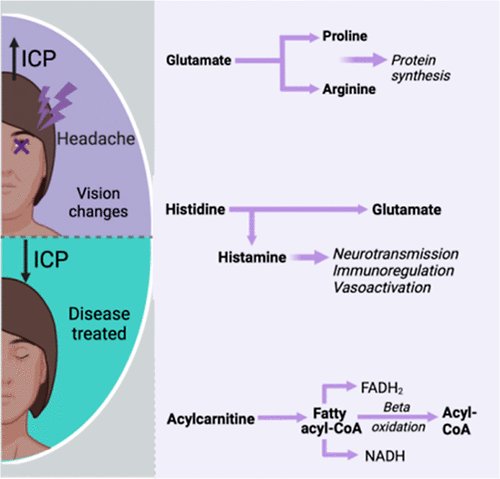

Dysregulation of Amino Acid, Lipid, and Acylpyruvate Metabolism in Idiopathic Intracranial Hypertension: A Non-targeted Case Control and Longitudinal Metabolomic Study.

Journal of Proteome Research.

2022,

22(4),

1127-1137,

ISSN: 1535-3893,

PMID: 36534069,